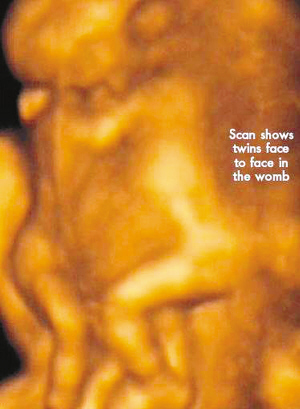

今年初,懷孕7周多的麗莎檢查發(fā)現(xiàn),懷上的竟是一對腹部緊緊相連的連體男嬰。這對連體嬰共享一只肝臟,雖然他們擁有各自的心臟,但兩顆心臟卻粘連在了一起。醫(yī)生建議麗莎立即接受流產(chǎn)手術(shù),他認(rèn)為麗莎腹中的連體嬰甚至無法活到她懷孕10周的時候。

麗莎每周都要到醫(yī)院接受醫(yī)學(xué)掃描,而她腹中的連體嬰也讓醫(yī)生感到驚訝不已,因?yàn)樗麄円呀?jīng)打破了醫(yī)生的死亡預(yù)言,一直在母親子宮中堅(jiān)強(qiáng)活到了現(xiàn)在。麗莎將于兩周內(nèi)接受剖腹產(chǎn)手術(shù)。